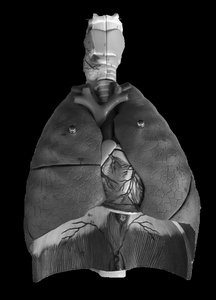

Lung Lobes and Fissures

Lobes of the Lungs

Right Lung: Three lobes – upper, middle, and lower.

Left Lung: Two lobes – upper and lower; contains the cardiac notch for the heart.

Fissures: Oblique and horizontal fissures separate the lobes.

Hilum: The entry/exit site for bronchi, blood vessels, and nerves.

Lung Histology

Microscopic Anatomy

Bronchioles: Small airways lined with cuboidal epithelium and surrounded by smooth muscle.

Alveoli: Tiny air sacs lined with simple squamous epithelium, the primary site of gas exchange.

Pulmonary Arteriole and Venule: Blood vessels involved in gas exchange.